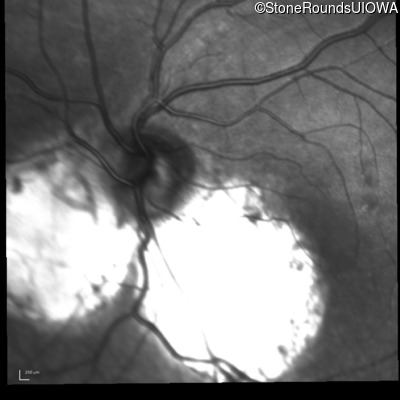

Age at visit: 8 years

Age at visit: 10 years

Age at visit: 11 years